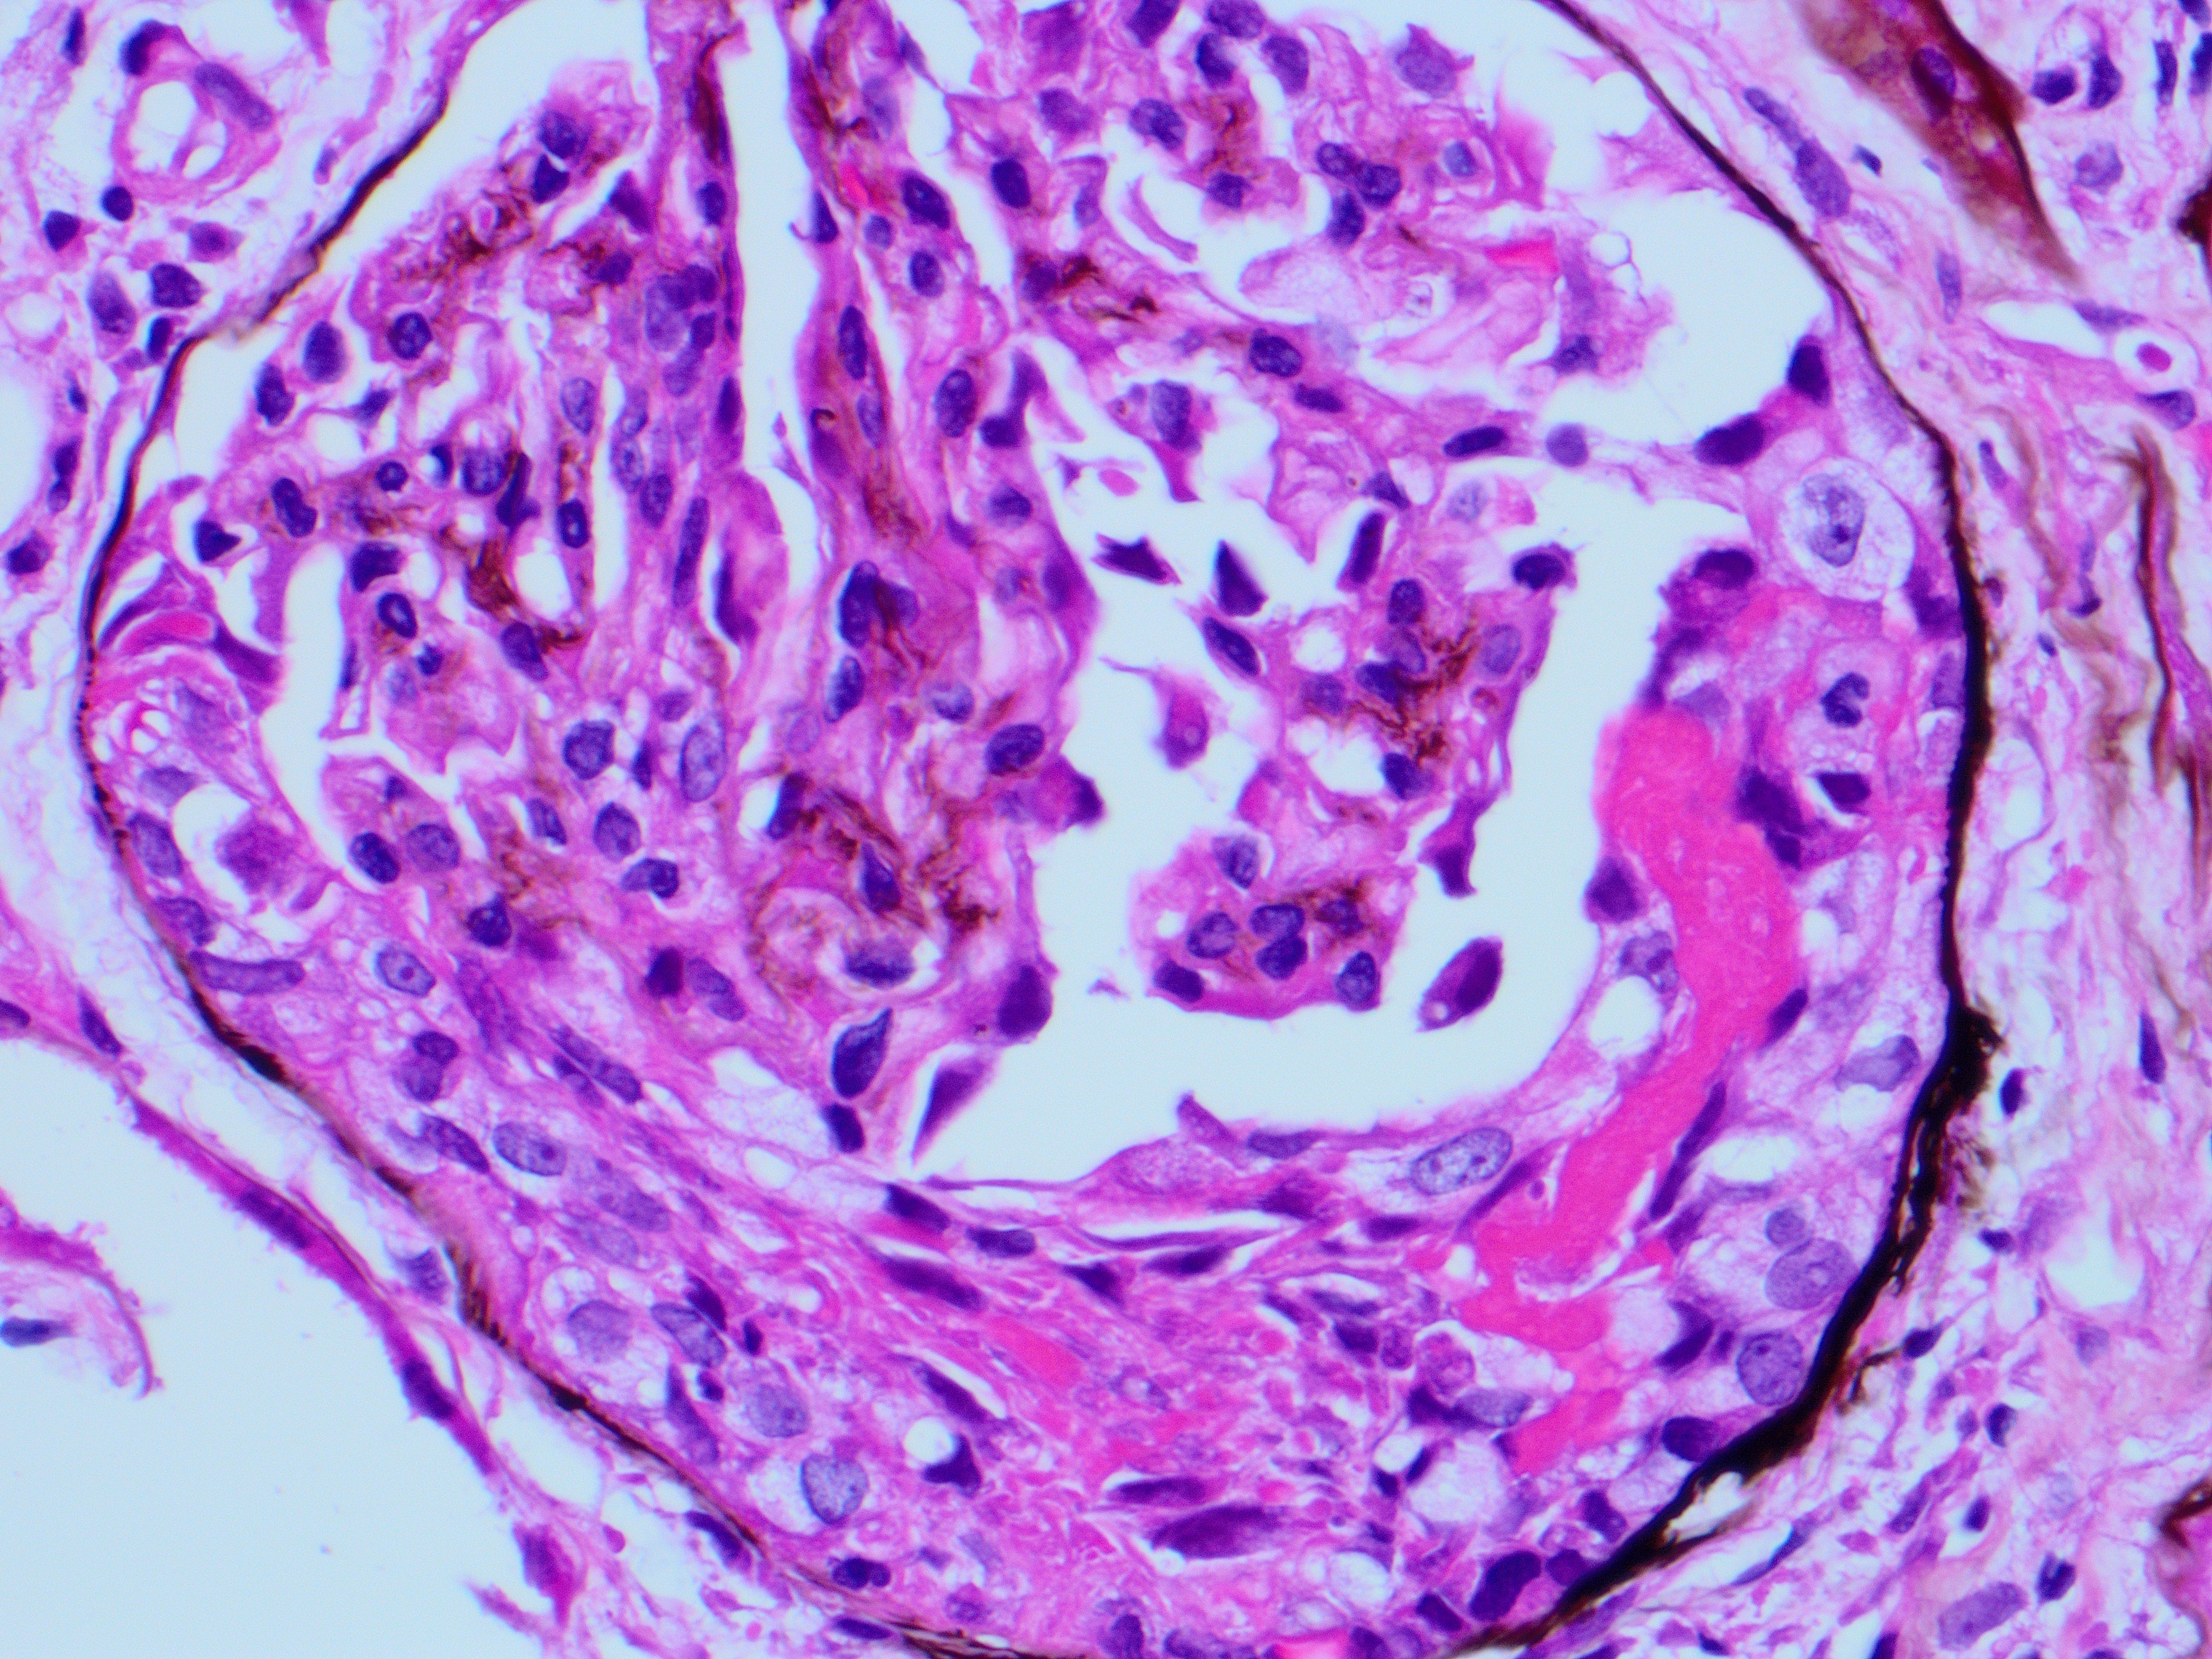

A 76-year-old man with a history of HTN and CKD Stage III presented with increased serum Cr. Renal biopsy performed showed cellular and fibro-cellular crescents with fibrinoid necrosis by LM (Jones silver, Fig a & b). IF and EM were negative.

The light microscopy in this case is showing crescentic glomerulonephritis (GN). The differential diagnosis for crescentic glomerulonephritis includes; 1) immune complex mediated GN, e.g., lupus nephritis (LN), 2) ANCA associated pauci -immune GN and 3) Anti-GBM antibody mediated GN. The diagnosis relies heavily on the clinical history and IF findings. The IF will show granular staining for immune complex deposits in LN and ANA will be positive. The anti-GBM antibody GN will show sharp linear staining along the GBMs by IF and anti-GBM antibodies will be positive. The ANCA associated GN typical shows no staining by IF. This patient was positive for cANCA, MPO and anti-histones antibodies. pANCA, PR-3 and anti-dsDNA were negative. The serology and IF findings were c/w ANCA associated GN. However, anti-histones antibodies are usually associated with drug related GN. Additional history on this case revealed that the patient was on hydralazine for BP control, which has resulted in vasculitis/ GN.